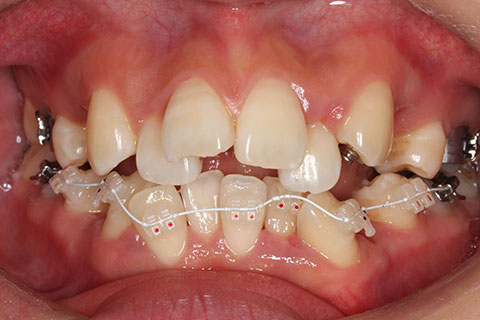

ハーフリンガル矯正3:上の歯のみ舌側矯正で治療(矯正期間24ヶ月)

治療前

治療中(開始直後)

治療中(開始半年後)

治療後

- 年齢・性別

- 25歳女性

- 治療期間

- 2年0ヶ月

- 抜歯

- 上下4番抜歯

- 治療費

- 110万円

- 治療内容

- 施術の副作用(リスク)

- 表側矯正と比較して、力学的な操作性が複雑なため、ボーイングエフェクトを起こしやすい。